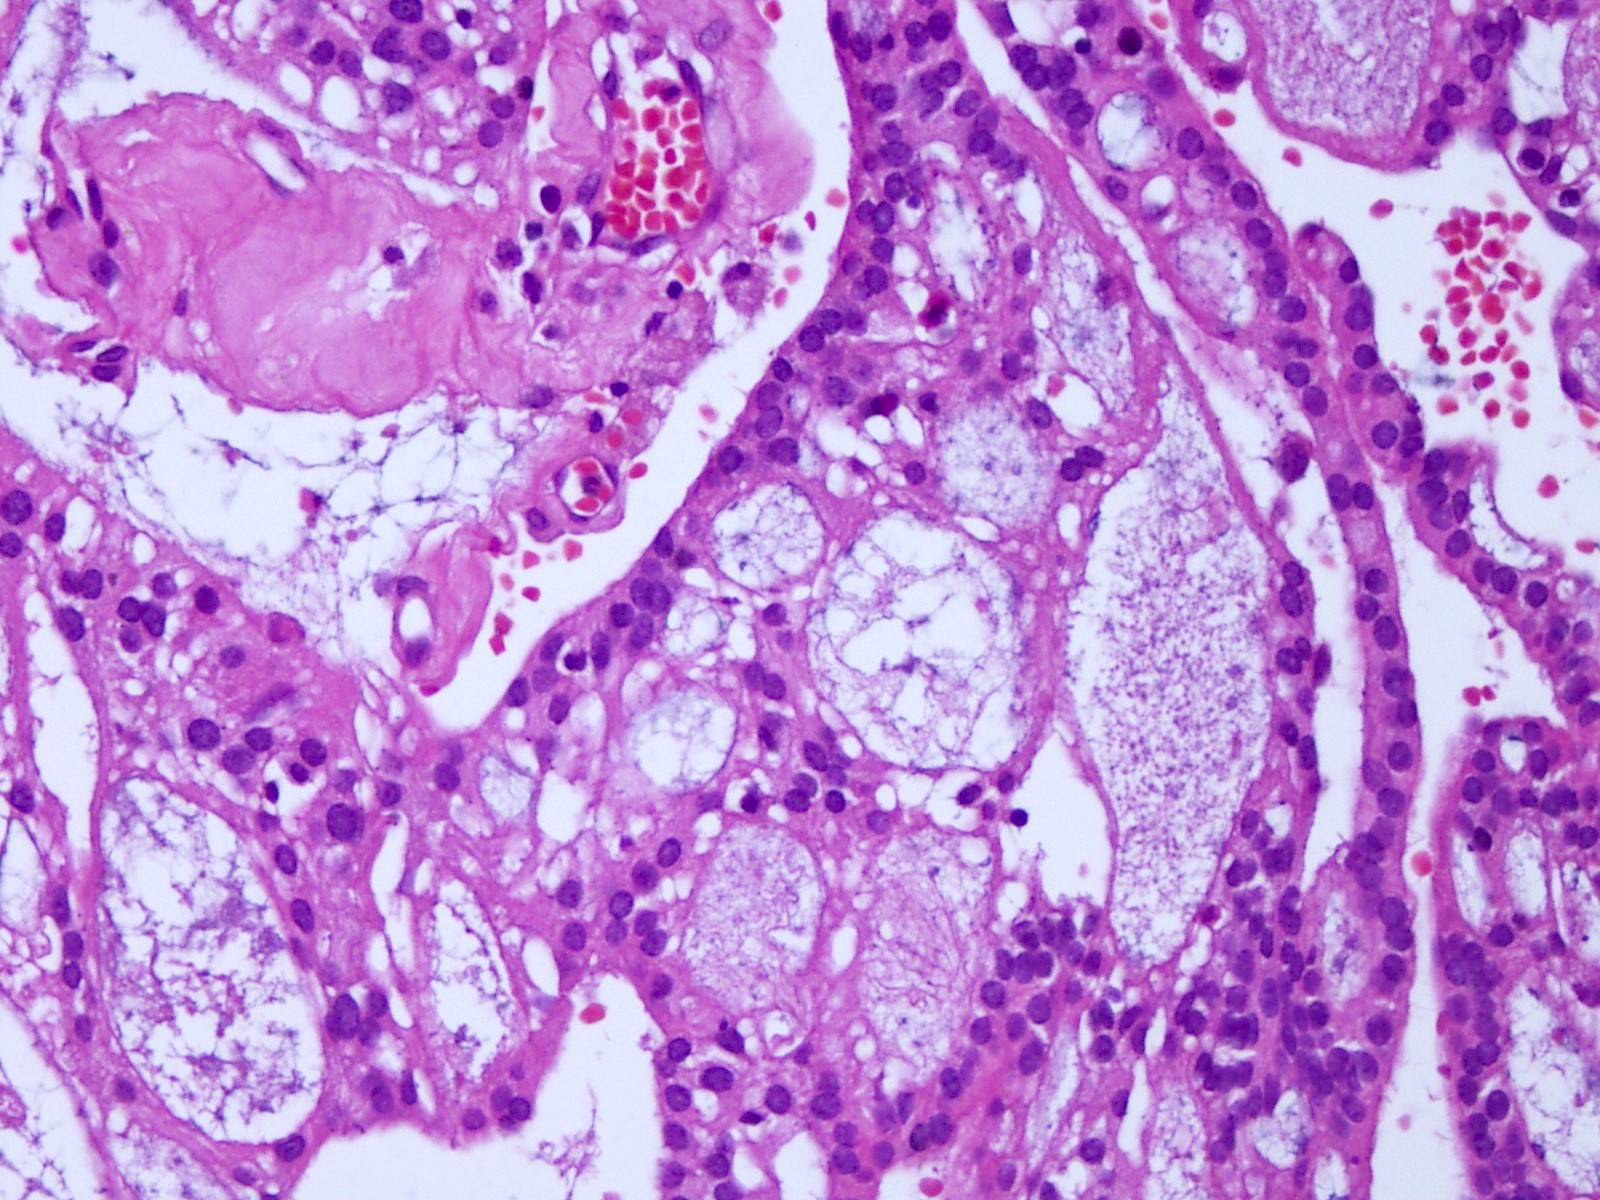

Microscopic (histologic) description

- Most common pattern is radial arrangement of cuboidal to epithelioid elongated glial tumor cells around hyalinized fibrovascular (central, often hyalinized blood vessels) cores in a papillary configuration

- Accumulation of basophilic myxoid material around blood vessels (myxoid stroma) and in microcysts

- Myxoid material is highlighted by PAS and Alcian blue positive staining

- In cases composed of confluent sheets of epithelioid cells with little or no papillary structures, PAS and Alcian blue positivity is useful in reaching a correct diagnosis

- Fascicular growth and spindle cells are common

- Pleomorphic tumor giant cells can be seen

- Occasionally tumor cells show distinctive eosinophilic balloons; these are PAS positive spherules that demonstrate spiculated reticulin staining (Am J Surg Pathol 1996;20:1091)

- Uncommon examples reported as anaplastic myxopapillary ependymomas show hypercellularity and reduced mucin in association with at least 2 of the following features: ≥ 5 mitoses / 10 high power field, Ki67 labeling index ≥ 10%, microvascular proliferation, spontaneous necrosis (Brain Pathol 2019;29:75)

Microscopic (histologic) images